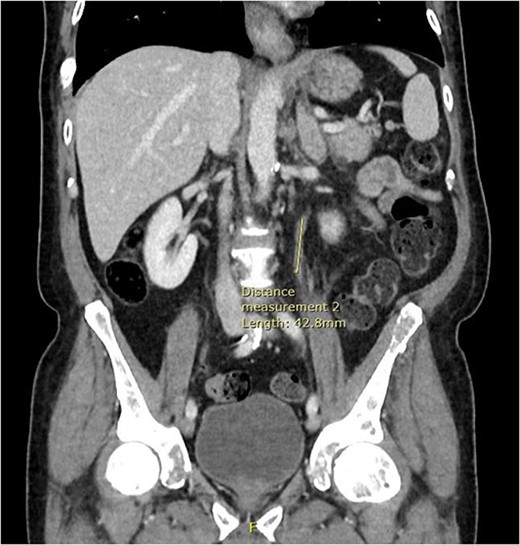

Computed tomography (CT) of the thorax, abdomen and pelvis was requested for staging. Lymphadenopathy was present superior and inferior to the diaphragm, left-sided hydronephrosis with reduced enhancement of the left kidney and widespread mixed lytic and sclerotic lesion affecting the skeleton. The bulky left adrenal gland was concerning for adrenal metastasis (Fig. 3). There was also abnormal urothelial enhancement in the left distal ureter for 4 cm, raising the suspicion of urothelial malignancy (Fig. 4). Blood tests showed a normal prostate specific antigen, mild acute kidney injury, CA19–9 of 17 256 and a carcinoembryonic antigen of 18.

Coronal CT abdomen and pelvis scan with contrast demonstrating left-sided hydronephrosis and left-sided adrenal mass (red arrow).